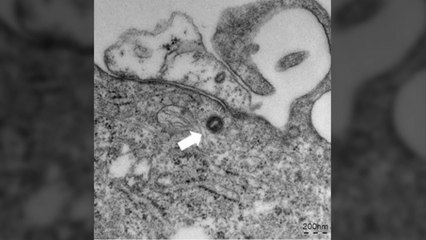

'원숭이두창'으로 알려진 엠폭스의 국내 여섯 번째 확진자가 나왔습니다. br br 해외에 간 적도, 해외에 다녀온 사람과 접촉한 적도 없어 첫 지역감염 사례로 추정됩니다. br br 방역당국이 감염 경로를 찾느라 비상입니다. br br 장아영 기자입니다. br br [기자] br 유럽과 미국을 중심으로 엠폭스가 한창 퍼지던 지난해 6월, 국내에서도 첫 확진자가 나왔습니다. br br [백경란 당시 질병관리청장 (지난해 6월 22일) : 국내에서도 원숭이두창 첫 환자가 발생하였습니다. 1명이라도 국내 확진자가 발생한 경우에는 절차에 따라서 '주의' 단계로 위기를 격상하게 됩니다.] br br 그로부터 열 달 뒤, 처음으로 지역사회 감염 가능성이 제기됐습니다. br br 해외에 간 적도, 해외에서 온 사람과 접촉한 적도 없는 확진자가 나온 겁니다. br br 국내 6번째 환자인 A 씨는 지난달 말 시작된 피부 발진이 낫지 않아 의료기관을 찾았고, 보건소에 엠폭스 감염 의심으로 신고된 끝에 확진 판정을 받았습니다. br br 앞서 국내에서 발생한 확진자 5명은 모두 해외에서 입국한 사람이거나 엠폭스 환자를 치료하던 의료진이었습니다. br br A 씨는 이들과도 연관성이 없는 만큼, 이른바 '숨은 확진자'에게서 병을 얻었을 가능성이 큽니다. br br 질병관리청은 A 씨의 동선과 접촉자를 조사해 국내 감염 경로를 확인하고 혹시 확진자가 더 있는지도 찾고 있습니다. br br [이재갑 한림대 의대 감염내과 교수 : 잠복기가 1~2주 정도 되니까요. 지난달 말이면 이제 접촉자에서 증상이 나타날 수도 있는 상황일 거거든요. 그래서 접촉자들에서 발병했는지 여부도 중요할 것 같고요.] br br 엠폭스는 호흡기 감염병과는 달리 피부나 성적 접촉과 같은 긴밀한 접촉을 통해 옮습니다. br br [이재갑 한림대 의대 감염내과 교수 : 잘 모르는 사람하고 성 접촉 이런 부분, 특히 피부 발진이 있는 분과의 접촉을 최대한 피해 주시는 게 좋고요. 그다음에 원인 모를 발열과 함께 발진이 동반되는 경우에 있어서는 빠른 시간 내에 엠폭스의 가능성이 없는지에 대해서 의료진하고 상담을 빨리 해 주시는 게 좋을 것 같습니다.] br br 전문가들은 최근 일본과 타이완을 비롯한 아시아 국가에서 엠폭스 발병 사례가 늘고 있다며, 지역사회 감염으로 확진자가 급격히 불어난 미국과 유럽의 전철을 밟지 않으려면 초기 역학조사가 중요하다고 강조합니다. br br YTN 장아영입니다. br br br br br ※ '당신의 제보가 ... (중략)br br YTN 장아영 (jay24@ytn.co.kr)br 영상편집 : 서영미br 그래픽 : 홍명화br br ▶ 기사 원문 : ▶ 제보 안내 : , 모바일앱, social@ytn.co.